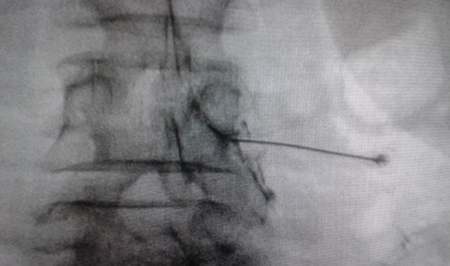

El acceso por vía transforaminal es el más utilizado (4). Se coloca al paciente en decúbito prono con una almohada a nivel abdominal para revertir la lordosis fisiológica. Las agujas o cánulas de radiofrecuencia que utilizamos con más frecuencia son de diámetro 20 o 22 G de 98 mm de largo con punta activa de 0,5 o 1 cm. Después de la asepsia con clorhexidina alcohólica y la colocación de campos estériles, se realizan enfoques radiológicos en incidencia anteroposterior, oblicuo y lateral. En incidencia anteroposterior y moviendo el arco en dirección cráneo caudal se borra el doble arco del borde inferior vertebral. En incidencia oblicua entre 20 y 30 grados ipsilateral al GRD a tratar, se visualizará la clásica imagen descrita como de “Scotty Dog”, que es resultado de acercar el macizo facetario y la apófisis espinosa al lado contralateral. El punto de entrada será entonces inmediatamente debajo del pedículo. Previa anestesia local con lidocaína al 1 %, la aguja se introducirá siguiendo una visión túnel y no se avanzará más allá de la mitad del pedículo en esta proyección con la finalidad de prevenir la lesión neural. En proyección lateral, se introducirá en el techo del neuroforamen

(Figuras 1 y 2) pero la localización final será determinada por la estimulación nerviosa sensitivo-motora. La estimulación sensitiva consiste en provocar parestesia o dolor en el territorio afectado con una estimulación entre 0,3-0,6 v. Durante la estimulación motora se pueden provocar fasciculaciones en el territorio afectado con un voltaje del doble al necesario para provocar las parestesias. Si se desea realizar una denervación intraganglionar, promulgada por algunos autores, la estimulación tanto sensorial como motora será positiva a menos de 0,3 v. Por tratarse de un procedimiento más doloroso, se aconseja administrar anestésicos locales después del estímulo doloroso y antes de realizar el tratamiento. La impedancia deberá mantenerse por debajo de 450 ohms, lo que se consigue infundiendo solución salina previa a la RF (4). La utilización de contraste constituye una buena práctica, ya que descarta la posición intravascular e intratecal de la cánula de radiofrecuencia.

Fig. 1. Vista radiológica de perfil que muestra una cánula de radiofrecuencia en el ángulo anterosuperior o techo del neuroforamen, topografía aproximada del ganglio de la raíz dorsal